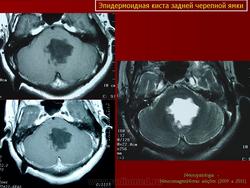

Эпидермоидные кисты задней черепной ямки

Эпидермоидные кисты задней черепной ямки - редкие новообразования. По данным Института нейрохирургии они составляют 0.5% от всех опухолей центральной нервной системы. Формирование морфологического субстрата эпидермоидных кист происходит на 3 неделе внутриутробной жизни, вследствие нарушения эмбриогенеза и смещения эпителиальной ткани в нервную трубку.

В большинстве случаев эпидермоидные кисты располагаются в ликвороносных путях головного мозга: в субарахноидальных цистернах или желудочковой системе. Распространение эпидермоидной кисты в пределах одной базальной цистерны встречается редко. Обычно, прорастая арахноидальные мембраны и трабекулы, переходят в соседние цистерны и занимают пространство, включающее несколько цистерн. Кроме этого, они способны прорастать твёрдую мозговую оболочку, разрушать костные структуры и расти экстракраниально.

Боковая цистерна моста довольно часто является местом первичной локализации эпидермоидной кисты. Дальнейший рост ее идет в направлении ската, супратенториально или в сторону краниоспинального перехода. При росте в направлении тенториального отверстия эпидермоидная киста распространяется в межножковую или охватывающую цистерны. При росте в сторону краниоспинального перехода, эпидермоидная киста через отверстия Люшка прорастает в полость четвёртого желудочка. Первичная эпидермоидная киста четвёртого желудочка аналогично может распространяться в мостомозжечковую цистерну.